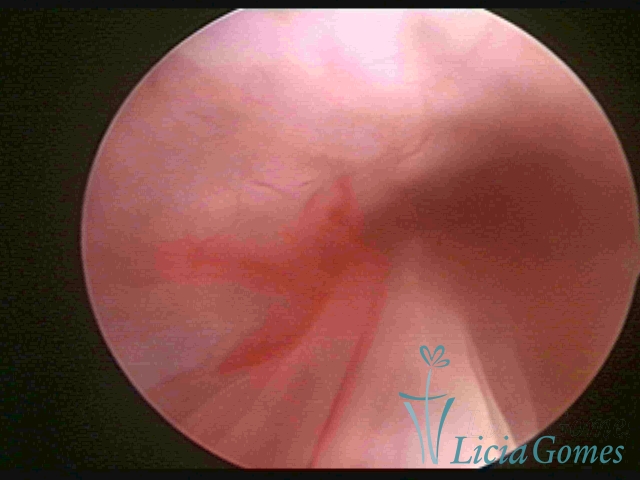

ENDOCERVICAL POLYPS

Benign tumors resulting from the reactive focal proliferation to inflammatory processes or hyperestrogenism situations, which may be sessile (with a large implantation) or stalked.